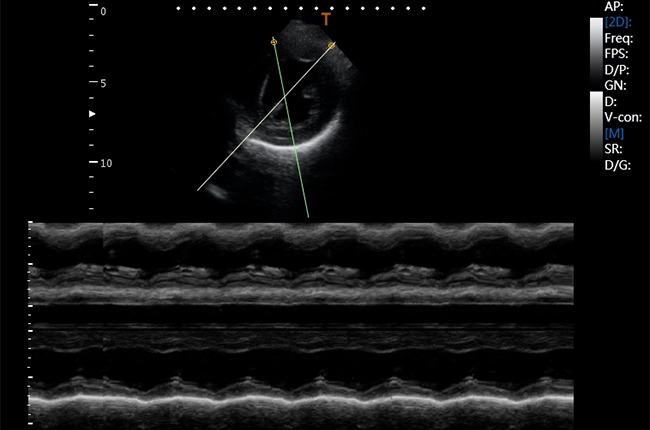

Імпульсно-хвильовий допплерівський режим

Тканинний допплер - оцінка рухливості тканних структур за допомогою допплерівської методики.

Кардіологія